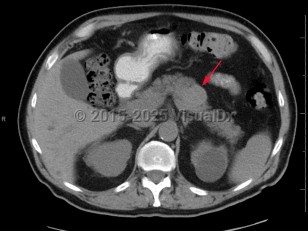

Pancreatic carcinoma

Patients typically present with advanced disease, as signs and symptoms can be very subtle, especially early in the disease. Classically described signs and symptoms include pain, jaundice, and weight loss.

Look For